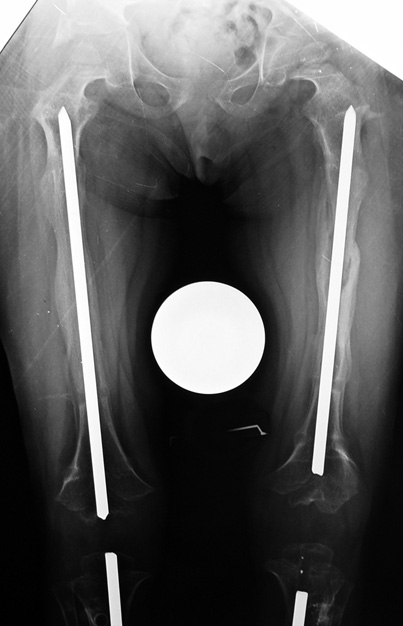

14 ve 16 yaşlar arasında her iki femurda toplam 10-12 cm boy uzatma her iki kalçanın fleksiyon deformitesinin düzeltilmesi (bu lomber hiperlordozu düzeltir) her iki kalçanın varus deformitesini düzeltme ortalama eksternal fiksasyon tedavi süresi = 10-12 ay